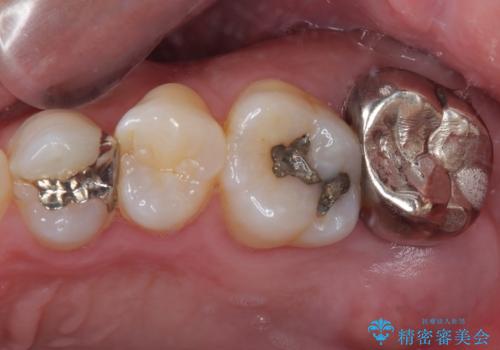

奥歯がしみる オールセラミッククラウンによる奥歯のむし歯治療